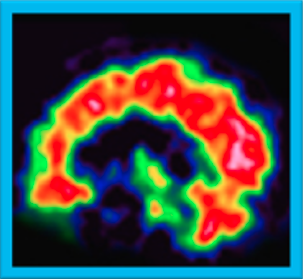

脳血流シンチグラフィは脳の血流状態を可視化する検査です。脳のどの部位で血流が保たれているか、あるいは低下しているのかを確認できます。

認知症の種類ごとに特徴的な血流低下パターンがあるため認知症の鑑別診断に役立ちます。

健康な人では、後部帯状回や楔前部および後頭葉などの血流が赤く映し出される。

アルツハイマー型認知症の人では、後部帯状回や頭頂葉内側の楔前部などで血流の低下がみられます